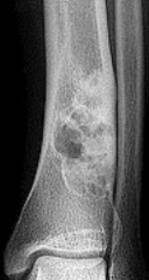

| What type of lesion is this? | Moth eaten and permeative (mixed increased and decreased density throughout the entire calcaneus) |